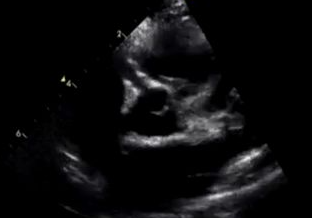

가와사키병은 명확한 혈액검사로 진단할 수 없기 때문에, 임상 증상과 심초음파 검사가 매우 중요합니다.

- 심초음파: 관상동맥 확장 여부 확인

**모든 환자에게 심장초음파(심초음파)**는 꼭 시행해야 합니다.

가와사키병에서는 초기 치료 후 시간 경과에 따른 관상동맥 변화를 관찰하기 위해 정기적인 심초음파가 필요합니다.